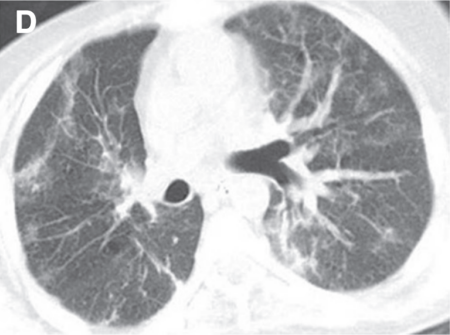

(3)非特异性间质性肺炎(NSIP):是CIP第二常见的报道类型,通常表现为肺下叶GGO和网状结构[17]

图片

(4)过敏性肺炎(HP):是CIP的一种相对不常见的放射学异常,弥漫性GGO和小叶中心结节,可见散在的空气滞留区[17]